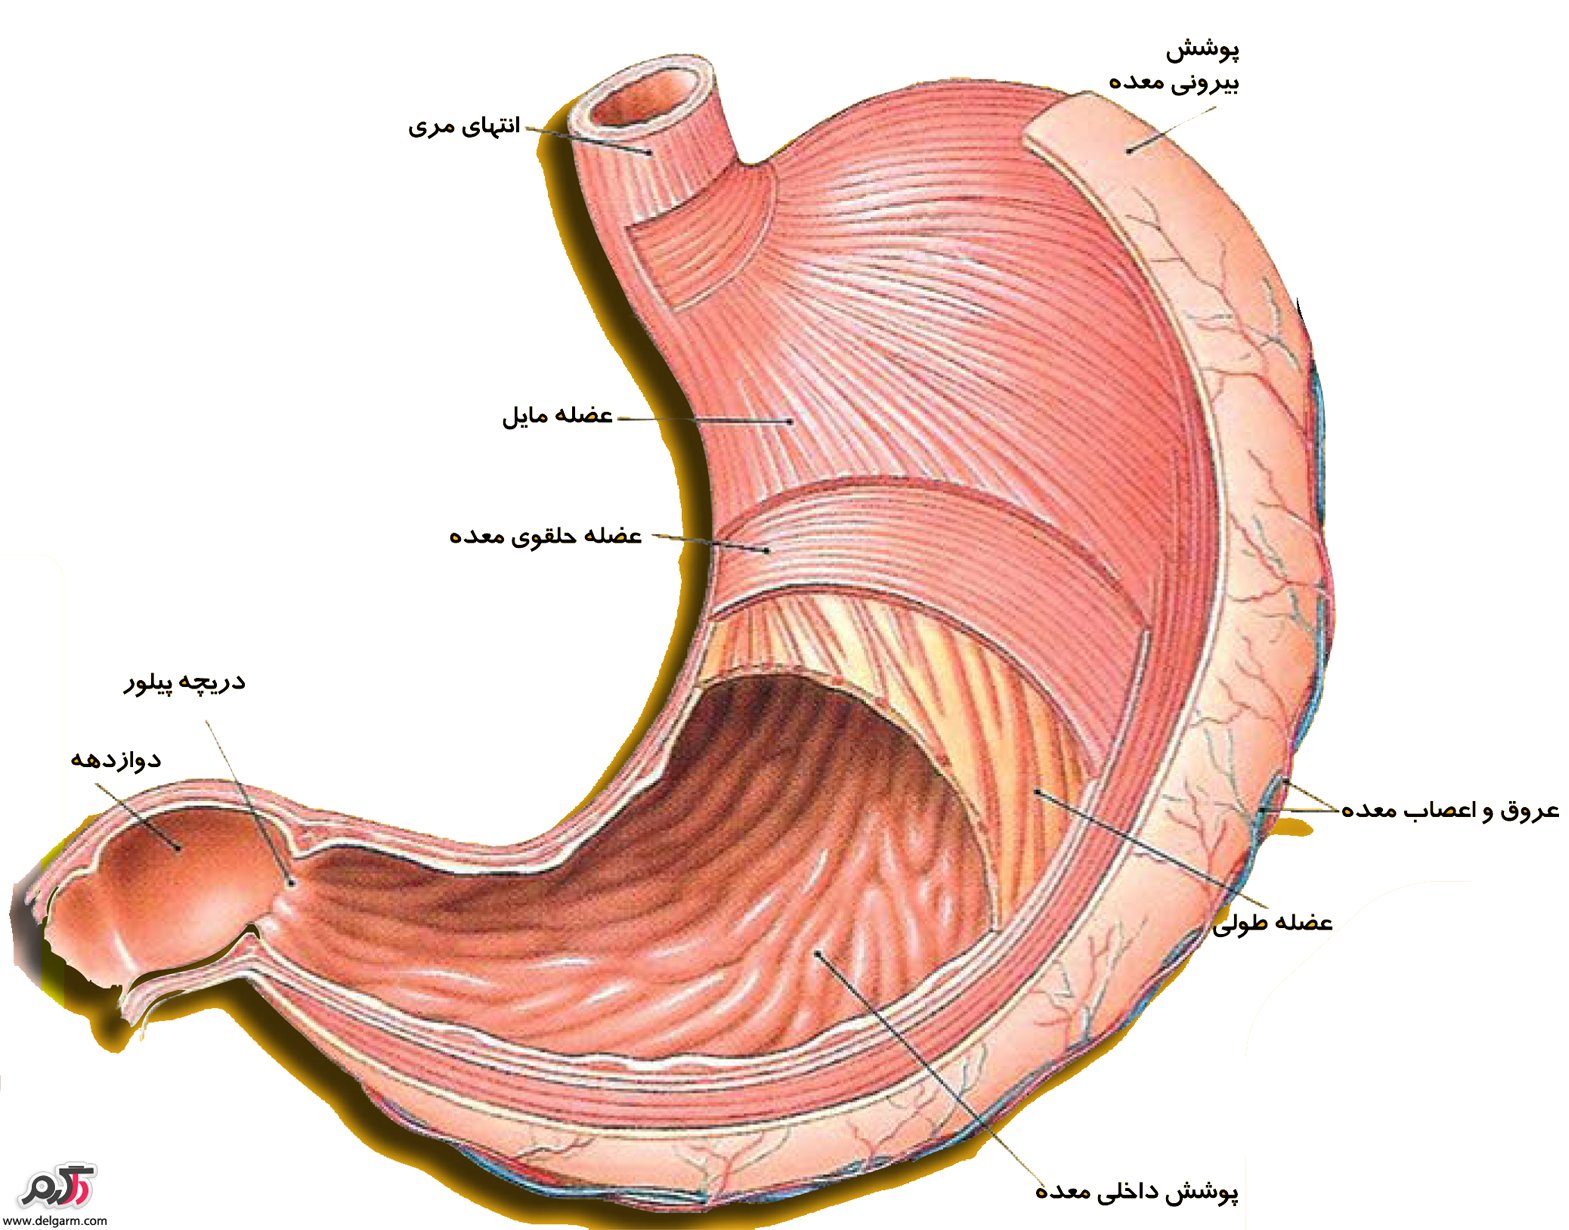

عکس داخل شکم انسان. در این همان طور که مشخص است شکم حالت بیضی شکل پیداکرده و این بیضی که کناره های شکم کشیده شده است. تعداد سلول های بدن انسان حدود ۳۷ ۲ تریلیون تخمین زده شده اند. Abdomen که در زبان عامه به غلط به آن دل نیز می گویند در آناتومی به قسمتی از تنه گفته می شود که مابین دیافراگم از بالا و سطح فوقانی لگن خاصره از پایین قرار دارد. ربات دیدنی ربات انساننمای چینی به صورت یک دختر جوان ساخته شده و جیا جیا نامگذاری شده است این ربات طوری برنامهریزی شده که میتواند صحبت کند و احساسات خود را از طریق تغییرات در چهره حالات.